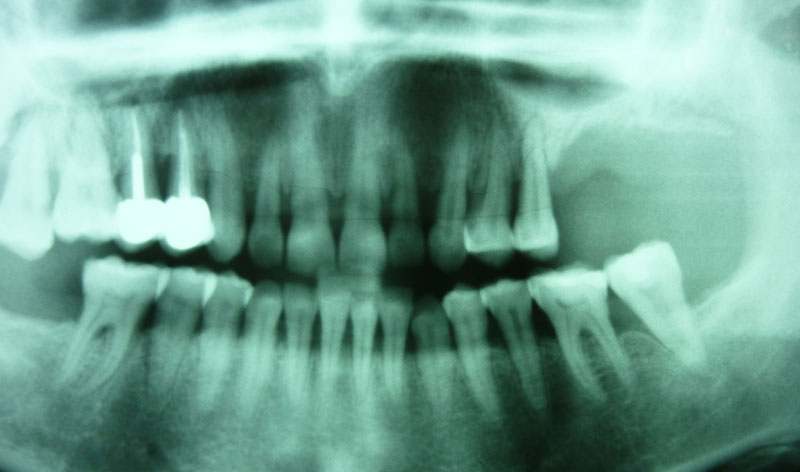

Se trata de una intervención que se efectúa bajo anestesia local. Está indicada en aquellos casos que requieren la colocación de implantes en el área posterior del maxilar superior donde el paciente no tiene el hueso suficiente para asegurar la fijación de los implantes.

Procedimiento: se realiza una incisión en la encía, se aborda el hueso maxilar superior realizando una pequeña apertura en el margen externo del maxilar, y se introduce un cemento formado por el propio hueso y sangre del paciente, y un material óseo conductor, que proporciona una serie de condiciones básicas para la formación de hueso.

Una vez realizada la intervención, en algunos casos se pueden colocar los implantes a la misma vez y en otros, es necesario esperar seis meses para que el material óseo forme un hueso con buena calidad que asegure el éxito de los implantes.